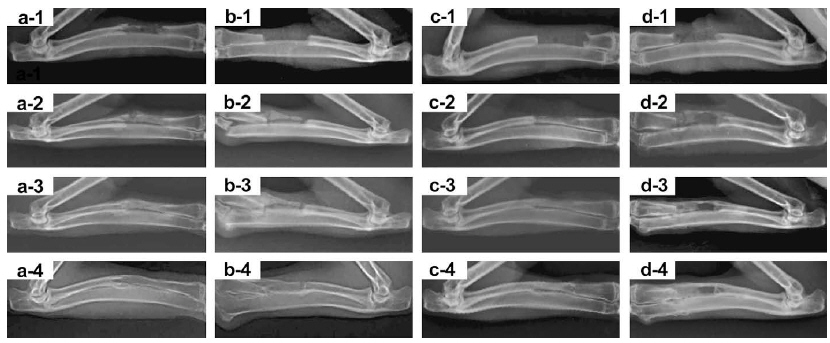

3.Biodegradable nanocomposites for bone repair.

Biomaterials, 2009, 30, 58-70